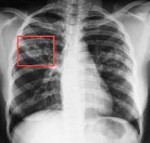

При подозрении на развитие заболевания (по симптомам и результатам общего осмотра пациента) следует сделать флюорографию или компьютерную томографию, чтобы оценить поражение легких. Если кашель продуктивный, необходимо взять образец мокроты для определения вида бактерий и проведения теста на чувствительность к антибиотикам. Пока проводятся анализы, пациенту следует назначить комбинированный курс противотуберкулезных препаратов.